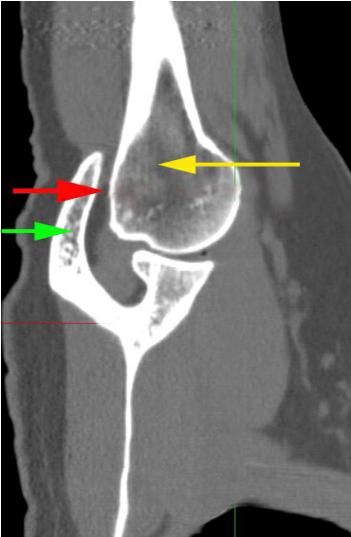

En esta imagen se puede ver el espacio creado (flecha roja) por el húmero (flecha amarilla) y el acromion (flecha verde):

Este espacio es el necesario para aliviar los problemas causados por el síndrome de pinzamiento subacromial, las lesiones del manguito rotador, el “hombro congelado”, y la gran mayoría de problemas de hombro.